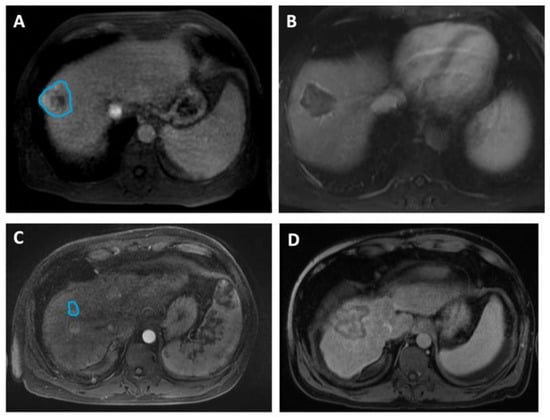

In Figure 2, we include representative MRI images illustrating visual differences in tumor heterogeneity between a Responder who underwent RFA, and a Non-responder who underwent MWA.

Figure 2. Four representative images illustrating differences in HCC tumor heterogeneity between two patients who underwent different ablation therapies and had contrasting treatment outcomes. (A,B) Axial MRI images of a 58-year-old male demonstrate (A) a 4.6 cm mass (manually delineated; blue ROI) in the right hepatic lobe, 5 days before RFA and (B) a 4.2 cm zone of ablation 50 days prior to the liver transplant. He remained recurrence-free during 1139 days of follow-up, up to the time of the transplant. The histopathologic review at the time of transplant reported complete necrosis. (C,D) Axial MRI images of a 49-year-old male illustrate (C) a 1.6 cm lesion (manually delineated; blue ROI) in the right hepatic lobe, 90 days prior to MWA and (D) a 5.1 cm ablation zone 5 days before the transplant. The patient underwent repeated procedures during the 366 days of follow-up, and exhibited incomplete pathologic response at the time of transplant.